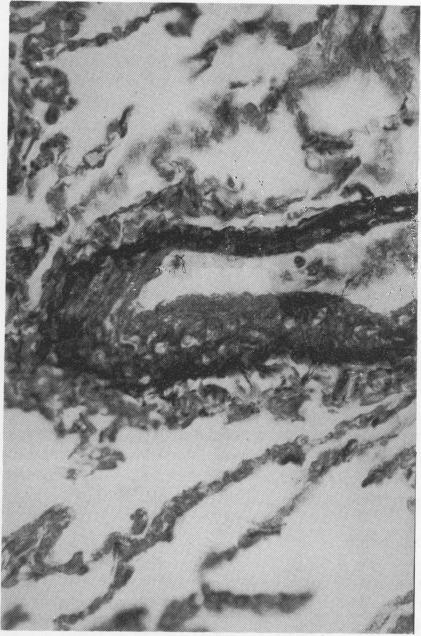

The thickness of the media of pulmonary veins and arteries was morphometrically assessed in 12 normal adults resident at altitudes over 3000 m and 12 resident at sea level. The pulmonary veins in the latter group were very thin walled. The average thickness of the pulmonary venous media in the group of highlanders was significantly thicker but this appeared to be due to prominent medial hypertrophy in seven individuals, five others having normal or near-normal pulmonary veins. In six of the 12 highlanders bundles of longitudinal smooth muscle cells occurred in the venous intima. There was close correlation between the thickness of the venous and that of the arterial media, suggesting an individual reactivity with a simultaneous response of all pulmonary vascular smooth muscle to high-altitude hypoxia. Hypertrophy of the media of pulmonary veins is likely to be an expression of venoconstriction and narrowing of the venous lumen may be enhanced by the development of longitudinal smooth muscle cells in the intima. Possibly venoconstriction is one of the factors responsible for high-altitude pulmonary oedema.

对居住在海拔3000米以上的12名正常成年人以及居住在海平面的12名正常成年人的肺静脉和肺动脉中膜厚度进行了形态测量评估。后一组的肺静脉壁非常薄。高原人群组肺静脉中膜的平均厚度明显更厚,但这似乎是由于7个人出现了明显的中膜肥厚,另外5个人的肺静脉正常或接近正常。在12名高原人中,有6人的静脉内膜出现了纵向平滑肌细胞束。静脉中膜厚度与动脉中膜厚度之间存在密切相关性,表明个体反应性以及所有肺血管平滑肌对高原低氧的同时反应。肺静脉中膜肥厚可能是静脉收缩的一种表现,内膜中纵向平滑肌细胞的发育可能会加剧静脉腔的狭窄。静脉收缩可能是导致高原肺水肿的因素之一。